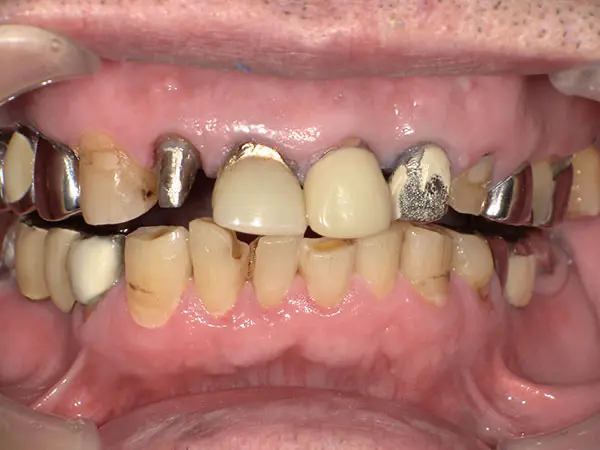

叢生・反対咬合

術前正面

術中正面

術後正面

術前上顎

| 主訴 | 歯のでこぼこ |

|---|---|

| 診断名あるいは主な症状 | 叢生、反対咬合 |

| 初診年齢 | 45歳 |

| 治療内容・装置 | マルチブラケット装置(上下表側からの矯正治療) MSE2 |

| 抜歯・非抜歯 | 下顎左第二小臼歯抜歯 |

| 治療期間 | 2年9ヶ月 |

| 費用 | 882,700円(税込) |

| 治療のリスク・副作用 | 歯の移動に伴う痛み 上下顎前歯部の歯根吸収 装置による口内炎 ブラッシング不良によるむし歯、歯周炎 |